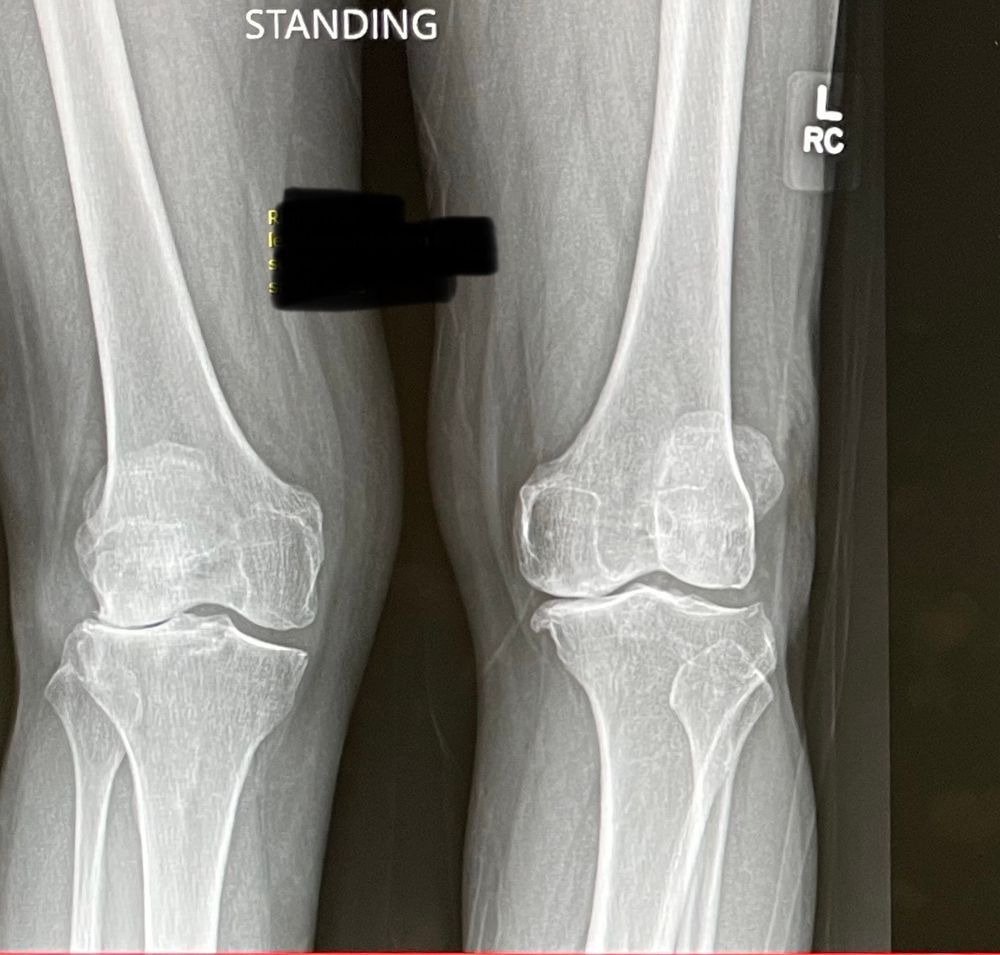

Here’s how they were managed. The lateral OA was found in the setting of advanced PF OA. The patient wanted a total. On the other side the PF joint was good and with no lateral symptoms a medial uni was a reasonable option —and was the patient’s first choice.

#orthopedics

It’s an interesting one because of all the patient teaching involved. Very different conversations with those options on the table.

Bilateral painful knees with windswept deformity. Pain in affected compartment only. If treating operatively what would you recommend: lateral and medial unis? Total and medial uni? Bilateral total?